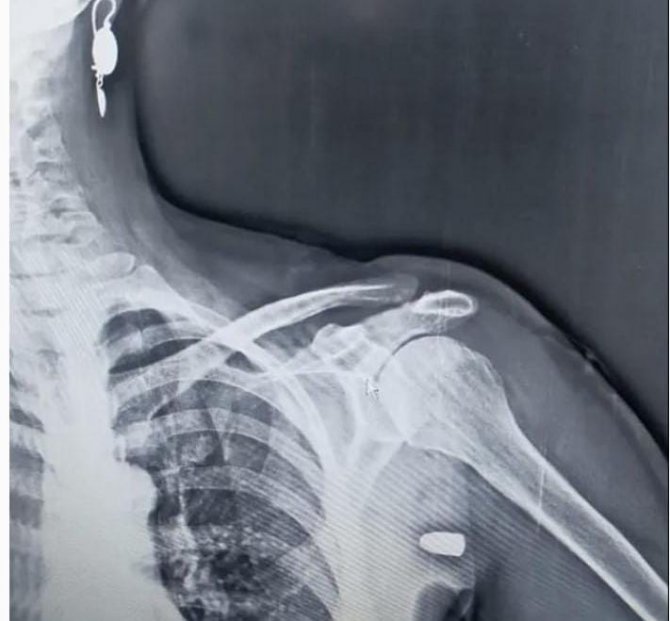

İlçenin Karaağaç Mahallesi yakınlarındaki Hırsafa Yaylası'nda ot biçen Asiye İnce (59), önceki gün yayla evinin yanındaki bahçede ot biçerken sol omuz bölgesinden giren yorgun mermi ile yaralandı. İnce, yakınlarının yardımıyla Tonya Devlet Hastanesi'ne kaldırıldı. Burada yapılan müdahalenin ardından Vakfıkebir Devlet Hastanesi'ne sevk edilen İnce'nin omuzundaki mermi çekirdeği ameliyatla çıkartıldı. Asiye İnce hastaneden taburcu edilirken, başından geçenleri anlattı.

Asiye İnce, yaptığı açıklamada "İneklerimi yedirdim. Bahçemde ot biçiyordum. Sert bir cisim omzuma çarptı. Elimi elbisemden içeri soktum, baktım kan akıyor. Kardeşimi aradım vuruldum dedim. Devletten bu silahları toplamasını istiyorum. Benim canım yandı başkalarının canı yanmasın. Hep haberler böyle olayları duyardım benim başıma da geldi. Hastanede film çekince mermiyi gördüler. Silah atanı bulsak şikayetçi olacağım. Bomboş arazideydim hiç tahmin etmezdim. Omzuma taş vurdular zannettim. Silahları hep toplasınlar bunlara silah vermesinler. Yaylaya çıkacağım ama korkuyorum bir daha o kurşun gelir diye" dedi.

Asiye İnce'nin eşi Yakup İnce (61) ise "O gün bende hastanedeydim. Telefonum çaldı hayırdır dedim. Orda dur vuruldum geliyorum dedi. Şaşırdım kimseyle alıp veremediğim yok. Hastaneye geldiler kurşun şah damarına 1.5 santim kala girmiş. Kalbe yakın bir noktada girmiş. Silahın eğitimli kişilere verilmesini istiyorum. Eğitimsiz her önüne gelenin silah almamasını istiyorum. Yaylada hiç böyle bir şeye rastlamamıştık. Allah'ıma bin şükür eşimi bana bağışladı" ifadelerini kullandı.